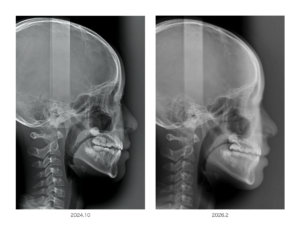

現在10歳の女の子ですが、もともと反対咬合の傾向があるお子さんです

この時のレントゲンを比較すると、やはり下顎骨が前に出ているような感じなのですが、今はその雰囲気は解消されています

ただここで注目すべきは向かって左の頚椎が変な弯曲を作っていることです

果たしてこれは偶然なのでしょうか?

もう一度横顔の写真を見てみると、昔の写真では妙に顎を引いている感じがしませんか?

これ「スウェイバック姿勢」と言いますが、このお子さんがお行儀よくするために顎を引いているわけではありません